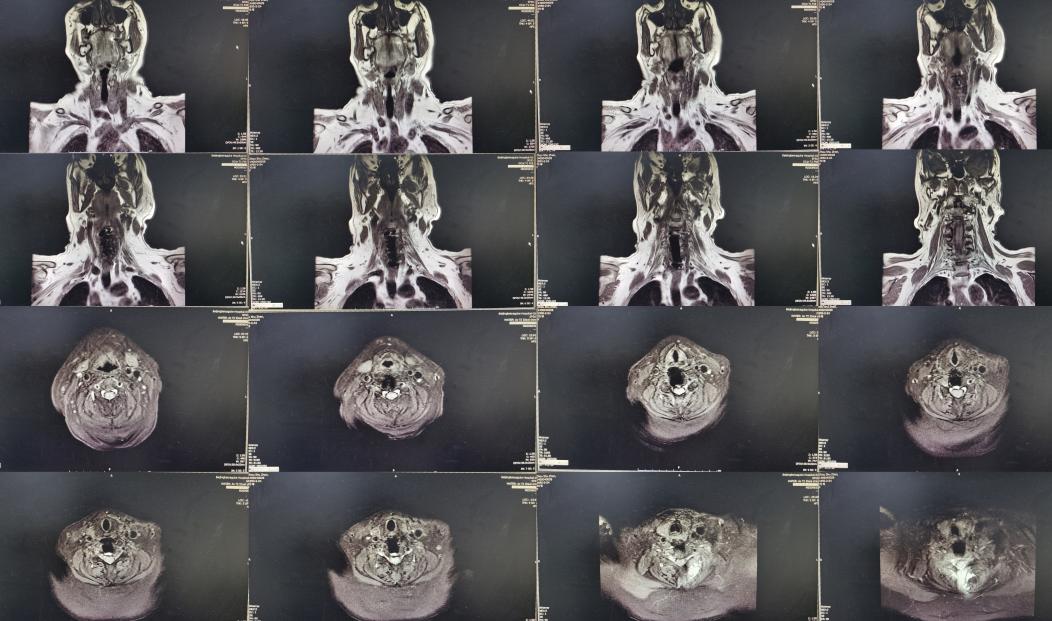

患者因间断性头晕、行走不稳,伴双上肢放射痛,麻木,于2020年4月11日入住北京某三级医院的中医骨伤科,当日查颈椎CT示椎管狭窄性颈椎病(图-1)。

图-1: 2020年4月11日颈椎CT

入院后第二天2020年4月12日查颈椎MR示颈椎病(脊髓型)( 图-2 )。

图-2: 2020年4月12日颈椎MR